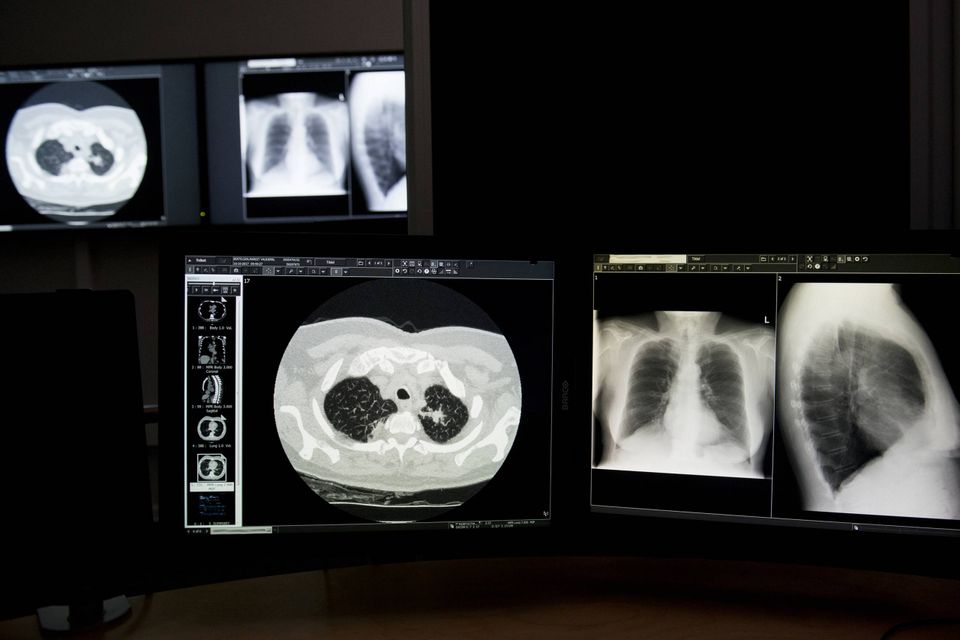

Styrelsen for Patientsikkerhed har afsluttet sin undersøgelse om genindkaldelse af patienter i lavdosis-CT-sagen på Regionshospitalet Silkeborg.

Alle patienter, som burde have været tilbudt en såkaldt fulddosis-CT-scanning på Regionshospitalet Silkeborg i perioden april 2019-februar 2020, har efterfølgende fået tilbudt den fulde undersøgelse af deres lunger.

Det konkluderer Styrelsen for Patientsikkerhed i et svar til Hospitalsenhed Midt, Region Midtjylland. På baggrund af en redegørelse fra netop Hospitalsenhed Midt konstaterer styrelsen dermed, at hospitalsenheden har fulgt Sundhedsstyrelsens anvisninger, som blev pålagt Region Midtjylland den 28. februar 2020. Inden da havde hospitalsledelsen i Hospitalsenhed Midt konstateret, at patienter på Regionshospitalet Silkeborg siden den 1. april 2019 fejlagtigt havde fået foretaget lavdosis-CT-scanning (LDCT) ved en lille mistanke om lungekræft. De skulle ifølge Sundhedsstyrelsens retningslinjer tilbydes en såkaldt fulddosis-CT.

En gennemgang af patienter visiteret til LDCT i perioden 1. 4.2019 - 29.2.2020 viste, at 132 patienter i stedet burde være visiteret til en fulddosis-CT-scanning. Alle henvisninger og visitationer blev primært gennemgået af to klinikere i Diagnostisk Center, Hospitalsenhed Midt. I de tilfælde, hvor der var forskellig vurdering fra de to klinikere, blev henvisning, visitation og relevante patientoplysninger sendt til ”second opinion” på Radiologisk afdeling på Odense Universitetshospital. Region Midtjylland konkluderede i sin efterfølgende redegørelse, af 132 patienter burde have haft tilbudt en fulddosis- frem for lavdosis-CT-scanning. Seks af patienterne blev efterfølgende henvist til kræftpakkeforløb.